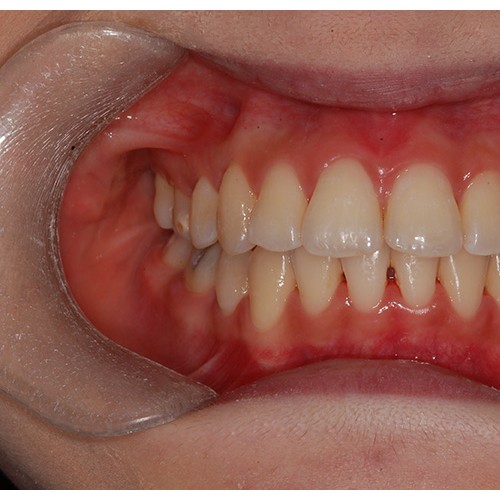

CHUNCHU'S ORTHODONTIC CLINIC# BEFORE_AFTER

춘추치과교정과를 방문해주신 분들의전후 사진을 확인해보세요.